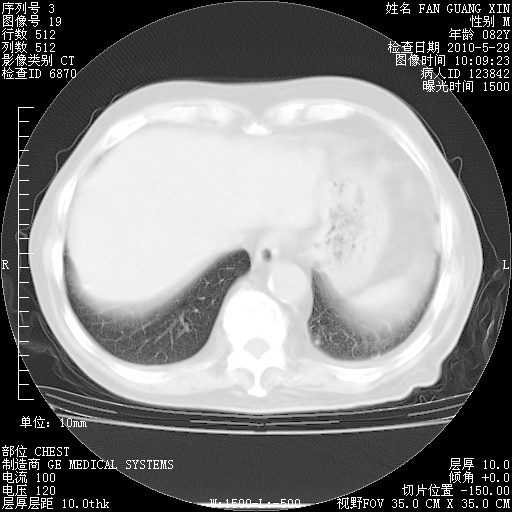

再治疗10天后的肺部CT

再治疗10天后的肺部CT 纵膈窗